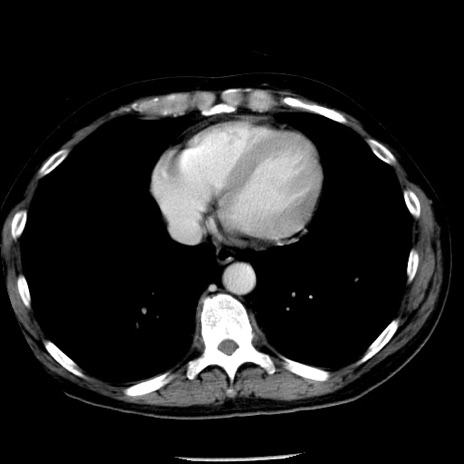

症例29(横断像)

【症例】40歳代男性

【現病歴】2日前から胃痛あり。徐々に周期的な激痛に変化した。本日になっても激痛があるため受診。

【身体所見】意識清明、BT 38-39℃台あり、腹部:膨満、やや硬、右下腹部に圧痛あり。

【データ】WBC 8500、CRP 23.26